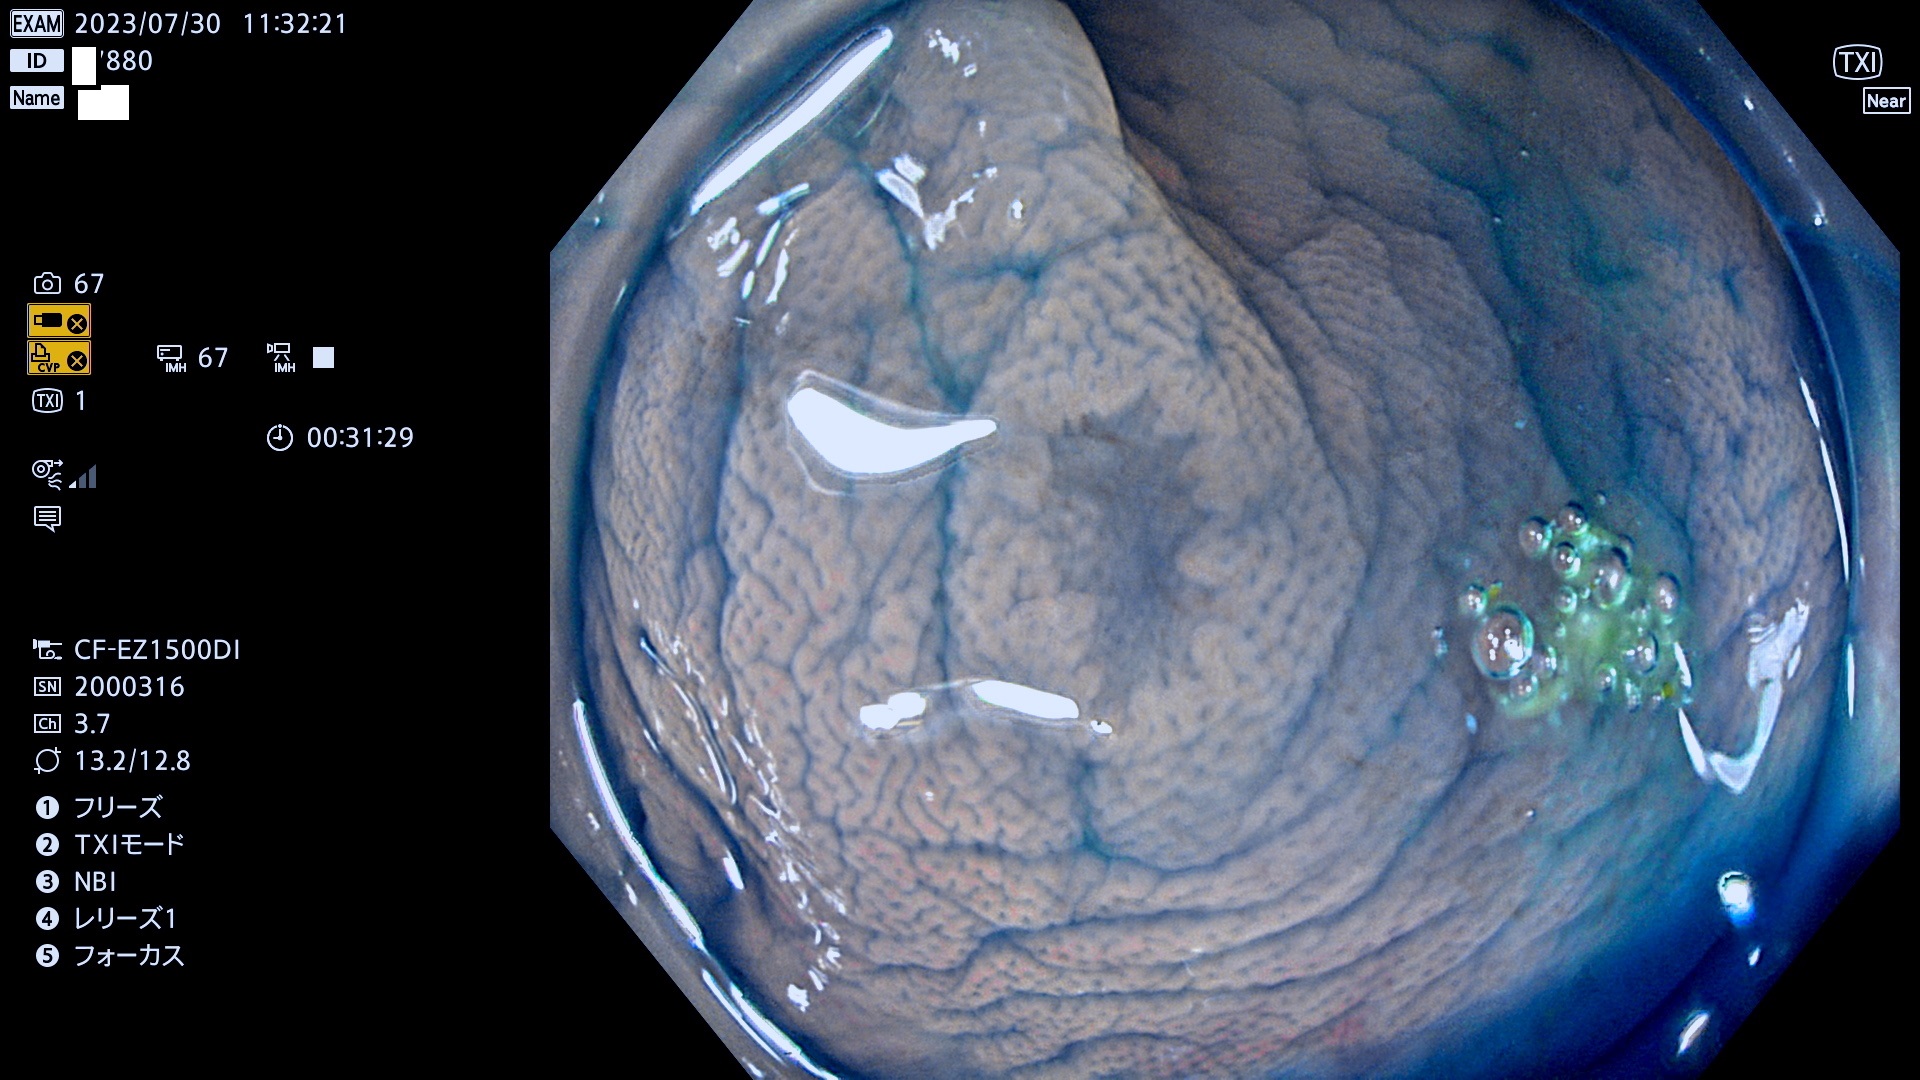

表面型腺腫(Flat Adenoma)の中で、完全に平坦な物をUb、陥凹している物をUcと呼びます。平坦隆起型(Ua)よりも、発見が難しく危険な病変です。このタイプは「内視鏡後・大腸癌の重要犯人」であり、この発見率は「腺腫発見率」よりも、重要な意味があります。

専門的)何故、陥凹していると危険? 癌遺伝子の変異が蓄積すると細胞分裂が盛んになり隆起するのでは?と通常は思われるでしょう。しかし実際は逆です。これは2022年の記事にある「細胞はストレスに直面したら細胞分裂を止める(細胞老化に入り休眠する)という生命の基本的現象」によるものです(Oncogene Stress)。細胞老化を起こすのが癌抑制遺伝子で、この安全装置(ブレーキ)が壊れると癌になります(休眠からの覚醒)。ですから陥凹は「まだ癌では無いが癌化の直前」を意味します。特に「小サイズなのに陥凹している」病変は短期間に腫瘍進化(⇒2021年記事)が起きたことを意味します(=ゲノム不安定性

専門的)Uc=De Novo癌? 内視鏡の解像度が低かった時代、このような説もありました。しかし今日の高精度内視鏡では良性の微小なUc型腺腫が日常的に見つかります。私見ですが「Ucこそが多段階発癌(Adenoma-Carcinoma Sequence)のMain Route」と考えます。

毎週の検査(木・金・土・日)に発見されたUb、Uc型・腺腫を、その週の日曜の夜にUPし1週間、提示します。

抽出の対象期間 2023年7月27日(木)〜7月30(日)の4日間(48件の検査)11件